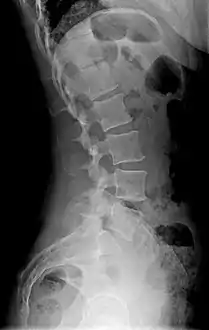

a,b)Cobb's angle for segmental lordosis and whole lumbar lordosis

X-ray of lumbar hyperlordosis

Measurement and diagnosis of lumbar hyperlordosis can be difficult. Obliteration of vertebral end-plate landmarks by interbody fusion may make the traditional measurement of segmental lumbar lordosis more difficult. Because the L4–L5 and L5–S1 levels are most commonly involved in fusion procedures, or arthrodesis, and contribute to normal lumbar lordosis, it is helpful to identify a reproducible and accurate means of measuring segmental lordosis at these levels.[16][17] A visible sign of hyperlordosis is an abnormally large arch of the lower back and the person appears to be puffing out his or her stomach and buttocks.

Precise diagnosis is done by looking at a complete medical history, physical examination and other tests of the patient. X-rays are used to measure the lumbar curvature. On a lateral X-ray, a normal range of the lordotic curvature of between 20° and 60° has been proposed by Stagnara et al., as measured from the inferior endplate of T12 to the inferior endplate of L5.[18] The Scoliosis Research Society has proposed a range of 40° and 60° as measured between the upper endplate of Th12 and the upper endplate of S1.[18] Individual studies, although using other reference points, have found normal ranges up to approximately 85°.[18] It is generally more pronounced in females.[18] It is relatively constant through adolescence and young adulthood, but decreases in the elderly.[18]